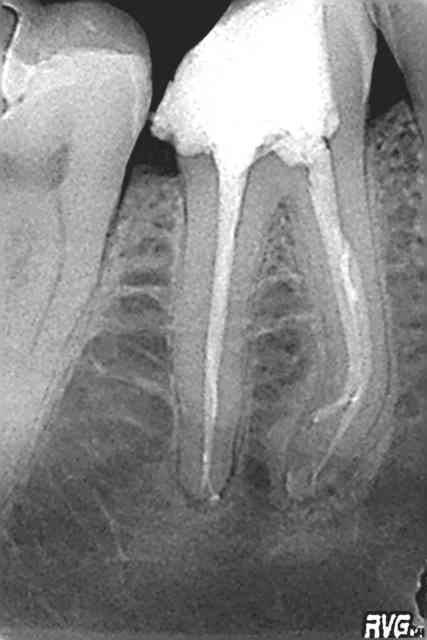

l'obturation, c'est a quoi?

Mc "MacSpadden" Hammer (Can't touch this)

Je suis étonné de la densité par contre, ça a bien poussé vers le haut pour un résultat pas si dense.

Allez j'en mets une autre, satisfaisante en densité

edit : tant que ya pas un mac spadden pété on est pas sur que c'est bien tassé :p

Non je rigole mais c'est l'instrument que je casse le plus, avec les limes K pour le cathétérisme. Jamais de protaper.

ça me pose pas de problème de le laisser noyé dans la gutta.